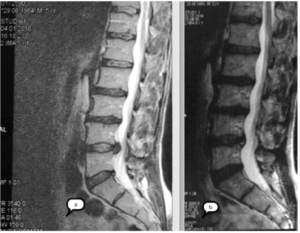

Интересными представляются также, пока единичные, резуль- таты долгосрочного посттерапийного наблюдения за пациентами с дорсопатией и выявленными экструзиями межпозвонковых дисков на поясничном и шейном уровнях. Проведение у данных пациен- тов расширенного обследования продемонстрировало клинически стойкое снижение уровня боли, точнее практически полное ее от- сутствие, а также регресс выявленных ранее грыж межпозвонковых дисков до 38% от исходных размеров и увеличение высоты межпо- звонковых дисков (рис. 2).

Рис. 2 МРТ поясничного отдела пациента Р., 52 лет до (а) и через 9 месяцев после (б) MBST-терапии